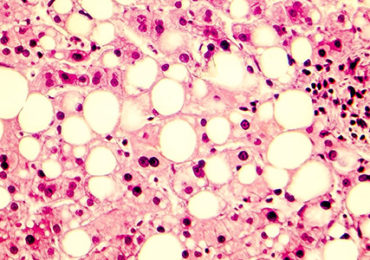

De microbiota, een nieuwe optie voor leververvetting

De bacteriën in de microbiota spelen een veelbelovende rol bij het bestrijden van leververvetting. Zo blijkt uit een grootschalige studie van Franse, ……